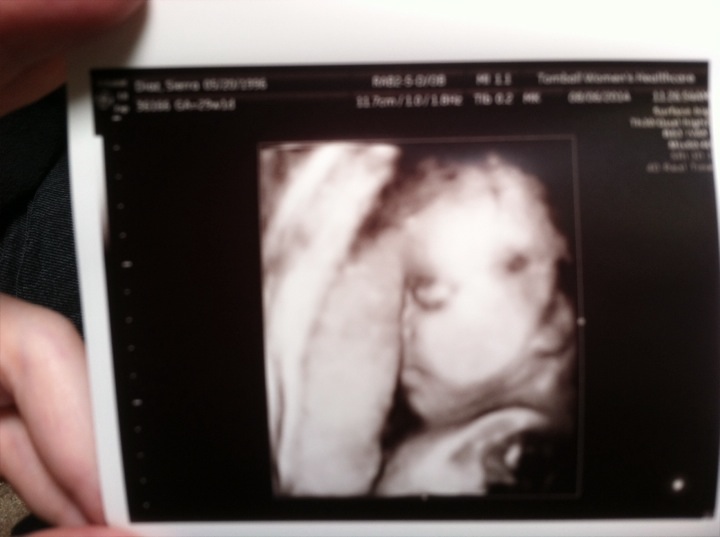

I'm a lot smaller than perhaps I should be I just got my 30 week ultrasound (yay) I was wondering if she sounds/looks right about on time she's 30 weeks and 3lbs she has lots of hair and full bodily development

• Yeah, that 3D pic is just what we need to know if she is doing well or not.

Seriously OP, talk to your doctor.